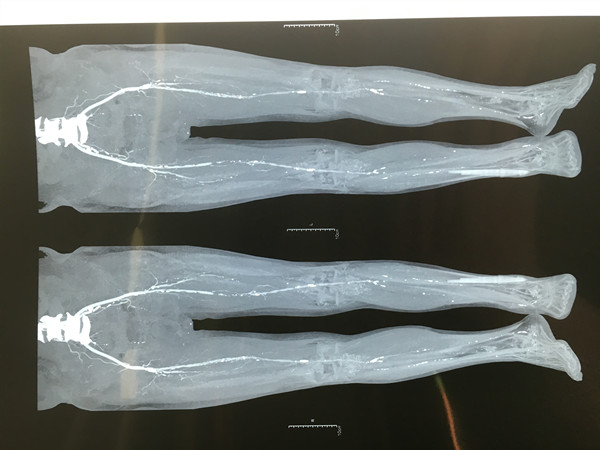

72岁的杨某罹患2型糖尿病已经20余年,平日非常注意血糖的控制,采用胰岛素规范治疗糖尿病,餐前血糖控制在6mmol/L,餐后血糖控制在8mmol/L左右。但不慎于2月前洗脚时将左足中趾皮肤搓烂,但就这一处小小的伤口始终难以愈合,自此经历了漫长的求医之路。入院双下肢CTA示:腹主动脉、双侧髂总动脉、髂内动脉及左侧髂外动脉硬化并狭窄;右侧股浅动脉、双侧腘动脉及左侧胫后动脉硬化并狭窄。经过贺西京主任、李浩鹏主任、李峰涛副主任医师、王放医师组成的治疗小组讨论后,决定对患者先行细菌培养检查,同时进行抗感染、伤口换药等治疗,待感染症状有效控制后,骨二科团队为患者行下肢横向骨搬移术,手术顺利。术后至今,患者双下肢疼痛明显好转,足趾创面未见进一步坏死。

术前双下肢CTA明确血管情况